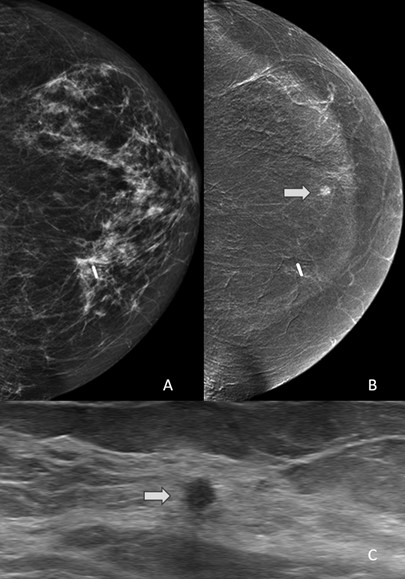

Of clinical importance is the fact that enhancing CEM-detected lesions that have an ultrasound correlate are more likely to be malignant. These data were also published by AJR in 2021 [8]. Among 153 enhancing lesions detected on CEM in 144 patients, the authors found ultrasound correlates in 47 (31%). Furthermore, this means that a substantial number of enhancing findings can potentially be sampled with ultrasound-guided biopsy (Fig. 3).